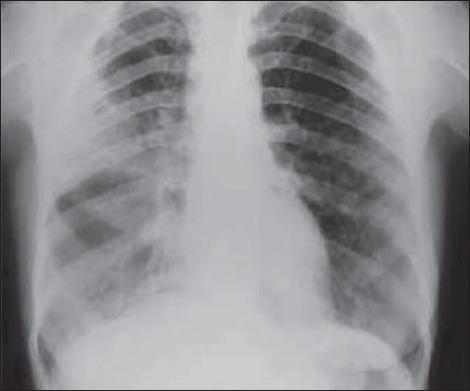

Esophageal achalasia is a motility disorder characterized by impaired relaxation of the lower esophageal sphincter and dilatation of the distal two-thirds of the esophagus. This condition may be a non-frequent reason of extrinsic compression of left atrium. In turn, this can be a cause of some hemodynamic changes such as chest discomfort, dyspnea or reduced exercise tolerance, systemic hypotension and tachycardia. We describe a case of a patient with esophagus achalasia compressing the left atrium and inducing hemodynamic compromise. The diagnostic methods, as chest X-ray, computed tomography (CT), manometry, and 2D-Trans-Thoracic Echocardiography (TTE) demonstrated the esophagus dilation, the impaired relaxation of the lower esophageal sphincter, and its compression on the left atrium. Three-D Trans-Thoracic Echocardiography (3D-TTE) was firstly performed also. This last examination pointed out better than 2D-TTE the extrinsic compression of the left atrium due to the esophagus dilatation. Therefore, 3D-TTE is a true improvement for the echocardiographic diagnosis of the left atrial compression induced by esophageal achalasia.

食管贲门失弛缓症是一种动力障碍性疾病,其特征为食管下括约肌松弛受损以及食管远端三分之二扩张。这种情况可能是左心房外部受压的一个不常见原因。反过来,这可能导致一些血流动力学变化,如胸部不适、呼吸困难或运动耐量降低、全身性低血压和心动过速。我们描述了一例食管贲门失弛缓症患者压迫左心房并导致血流动力学损害的病例。胸部X线、计算机断层扫描(CT)、测压法和二维经胸超声心动图(TTE)等诊断方法显示了食管扩张、食管下括约肌松弛受损以及其对左心房的压迫。还首次进行了三维经胸超声心动图(3D-TTE)检查。最后这项检查比二维经胸超声心动图更清楚地显示了食管扩张导致的左心房外部压迫。因此,三维经胸超声心动图是食管贲门失弛缓症所致左心房压迫的超声心动图诊断的一项真正进展。